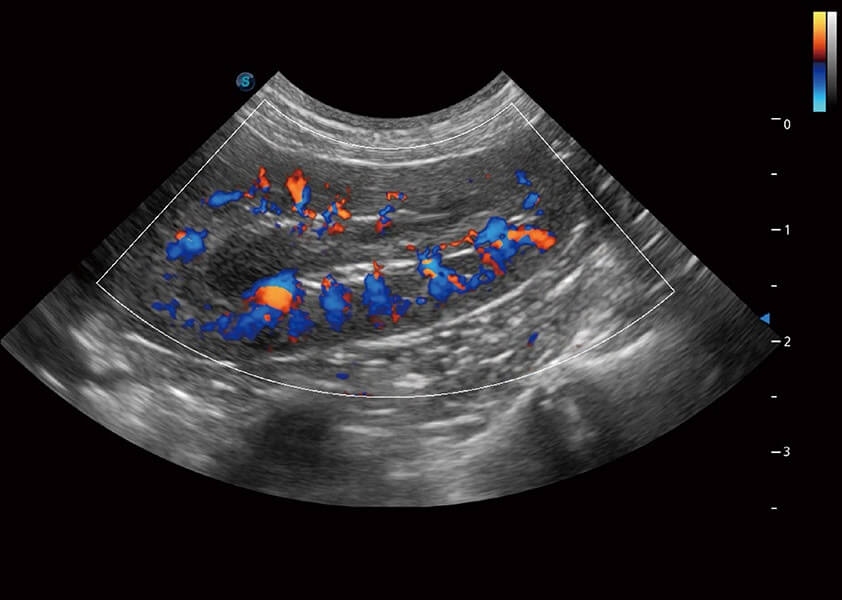

SR Flow 高分辨率血流成像

能够清晰显示细小、低速血流图像,获取传统彩色多普勒技术难以得到的细节和信息。

Micro F 显微血流成像

通过创新的Matrix E自适应滤波器和超长时间域算法,极大提升超低速微细血流的检出能力,同时更精准地滤除软组织和噪声信号,为兽用医生提供以往无法通过常规血流获得的疾病诊断信息。

(犬)肾脏血流